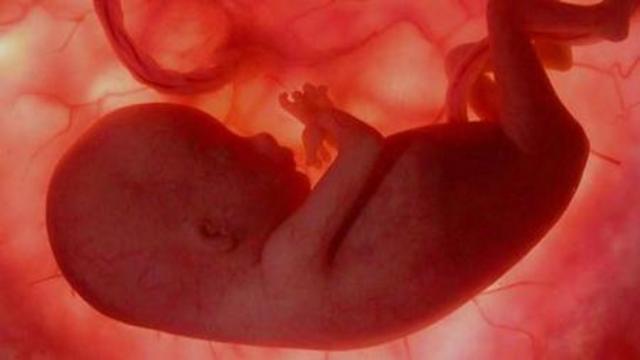

• Semana 20

Semana 20

La piel es de un color rojizo porque todavía no ha acumulado suficiente grasa debajo de ella, aunque se empieza a engrosar y ya cuenta con sus respectivas capas.

Se empieza a formar el paladar y las papilas gustativas se encuentran en toda la boca y no solo en la lengua, sino alrededor de ella, en el área de los labios e incluso en las mejillas.

El bebé ahora chupa el pulgar, juega con el cordón umbilical y se entrena con sus puños.